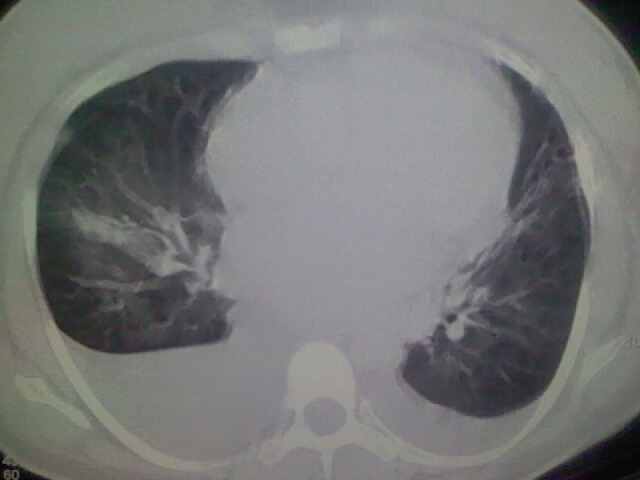

女,24,剖腹产后,突觉胸痛,干咳,不能平卧

胸水 感染 心影增大 肺水肿?

双肺“肺泡性肺水肿” “胸腔积液”!

双侧胸腔积液,肺泡性肺水肿。后纵隔好像有占位。

考虑肺梗塞、肺水肿,双侧胸腔积液

肝脾大,双侧胸腔积液,双肺水肿,肺动脉[包括远端小动脉],左右心房,左心室增宽,右心室主动脉无明显改变,符合左心功能不全征;;建议除外二尖瓣关闭不全,扩张性心肌病